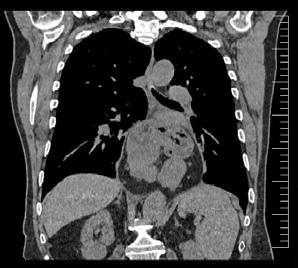

Cazuri disperate în chirurgia cardiacă –atunci când abordul minim invaziv este soluția

Dr. Ion Iovu, Prof. Univ. Dr. Lucian Dorobanțu, Dr. Andreea Bogdan, Dr. Ioana Băjenaru, Dr. Oana Ioniță, Dr. Mădălina Cojocaru, Dr. Toma Iosifescu, Conf. Dr. Cătălin Badiu, Dr. Alexandru Vasilescu